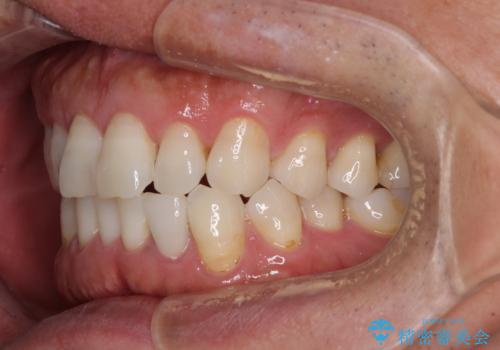

内側にある歯が干渉する 上顎前歯の部分矯正

- 上顎の前歯が内側にあり、下顎のセラミッククラウンと干渉することが気になるとのことで来院された患者様です。

上顎前歯にワイヤー装置を装着し、セラミッククラウンとは干渉しないようにしながら歯列を整えることとしました。

セラミッククラウンとの干渉はすぐに改善され、歯列も整いましたが、一方で、前歯で食事が噛みにくくなり、1年近い治療期間となりました。